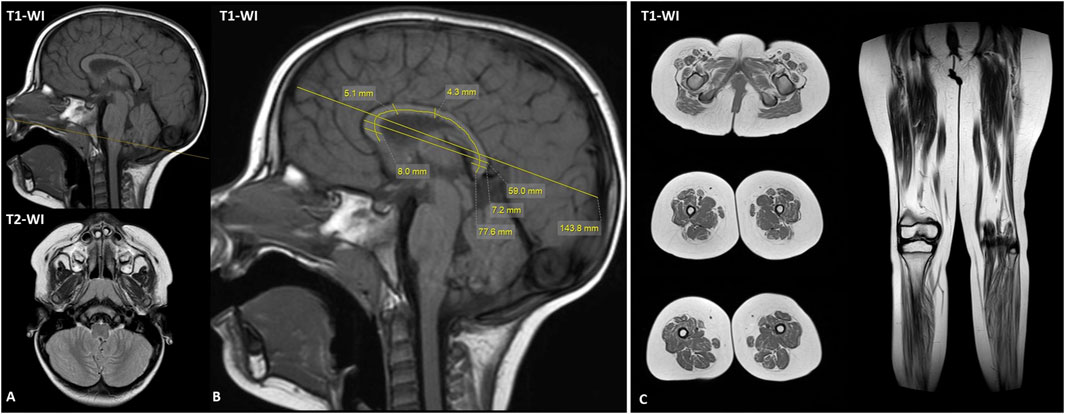

The brain MRI at the age of 3 years appeared unremarkable, without any structural brain anomalies (Figure 2). Corpus callosum morphology was carefully evaluated in the patient (Figure 2B). Measurements were compared with the age- and sex-specific centile tables followed by (Garel et al., 2011), and all fell within the normal range (between the 3rd and 97th centiles) for 3-year-old girls. Lower limb muscle MRI demonstrated diffuse fatty infiltration of lower leg and thigh muscles on T1-weighted images, indicative with a neurogenic pattern (Figure 2C). The adductor longus and adductor magnus were relatively spared. T2 STIR images showed hyperintensity in the posterior compartment of lower leg muscles.

FIGURE 2

Magnetic resonance imaging of brain and lower limb muscles. (A) Brain MRI shows no structural brain abnormalities. (B) The brain MRI demonstrated normal range corpus callosum measurements for 3-year-old female proband. (C) The lower limb muscle MRI revealed diffuse fatty infiltration predominant in lower legs. T1-WI, T1 weighted image; T2-WI, T2 weighted image.

The phenotypic spectrum of the KIF21A-related disorders is broad and includes CFEOM, and several reports linking them to inherited distal arthrogryposis (Engle et al., 1997; Falb et al., 2023). Some clinical-phenotypic correlations have been established. Specifically, heterozygous missense variants are most frequently associated with CFEOM, a congenital, non-progressive ophthalmoplegia with or without ptosis and usually without central nervous system malformations (Yamada et al., 2003). CFEOM results from a malformation of cranial motor nerves and their neurons (Demer et al., 2005; Cheng et al., 2014). The oculomotor nerve is consistently the most markedly hypoplastic cranial nerve, though hypoplasia of the abducens nerve is also observed. Although extraocular manifestations are less common, several patients with typical congenital bilateral ptosis/ophthalmoparesis have shown cerebellar vermis atrophy and adult-onset cerebellar signs, without peripheral neuropathy (Di Fabio et al., 2013). Biallelic loss-of-function KIF21A variants were associated with more severe phenotypes, as a fetal akinesia with multiple arthrogryposis, brain malformations, pulmonary hypoplasia, and facial dysmorphisms (Falb et al., 2023; Bhola et al., 2024). The isolated distal motor phenotype was not previously described in the literature. Notably, although the corpus callosum of our patient appeared similar to that in the case report of Borja et al., all measurements fell within age-appropriate normal and we also did not observe other structural brain abnormalities. Our proband was clinically diagnosed with distal motor neuropathy supported by the nerve conduction study, needle electromyography and lower limb muscle MRI findings. Notably, the proband’s medical history also included reports of forceful, unprovoked vomiting during the first years of life, as reported in the previous KIF21A p. (Leu664Pro) case. Interestingly, our patient’s intermittent exotropia contrasts with the persistent strabismus seen in (Borja et al., 2025). The phenotype of motor neuropathy clearly predominates in our proband (Table 1).